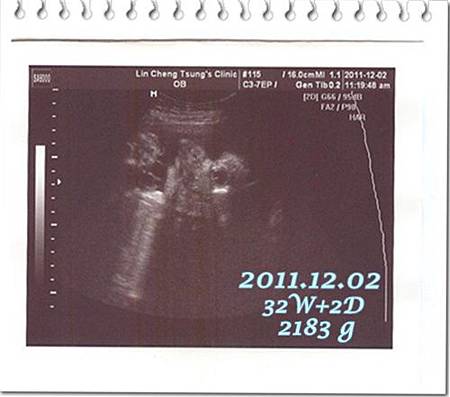

倒數的最後一個月

每個星期都得去做例行性產檢

索性累積四次再PO一篇文

記錄一下二寶的健康狀況…